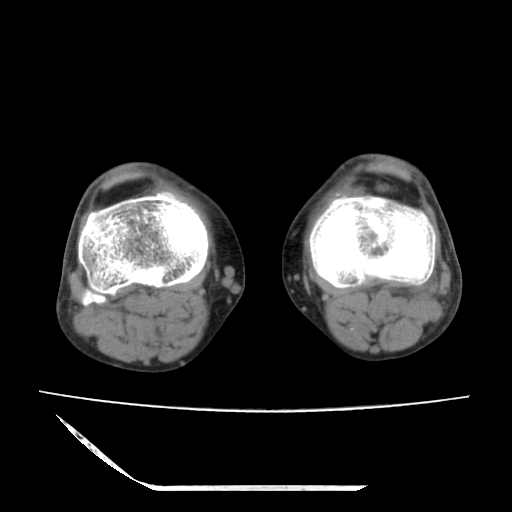

标题: CT13225:老年男性,左膝关节疼痛数月;请各位老师讨论。 [打印本页]

标题: CT13225:老年男性,左膝关节疼痛数月;请各位老师讨论。

骨质增生,骨性关节面硬化,关节积液,考虑退行性骨关节病

关节腔内少量积液,关节面退变。

双膝退变

骨质增生,骨性关节面硬化,关节间隙失常,关节积液,考虑退行性骨关节病.

这个病例诊断:退行性骨关节炎